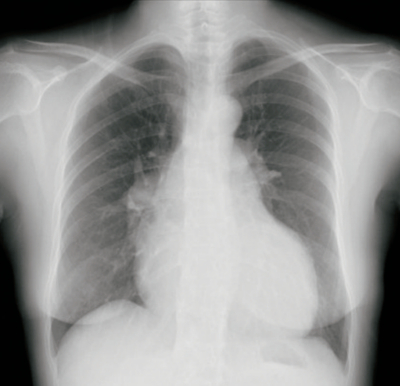

血液所見:赤血球 390万、Hb 12.0 g/dL、Ht 34%、白血球 6,600、血小板 9万。血液生化学所見:総蛋白 6.2 g/dL、アルブミン 3.3 g/dL、ALT 26 U/L、クレアチニン 0.6 mg/dL。CRP 0.1 mg/dL。胸部エックス線写真及び心電図を示す。

この患者の息切れの原因として、最も考えられるのはどれか。

a. 肺高血圧症